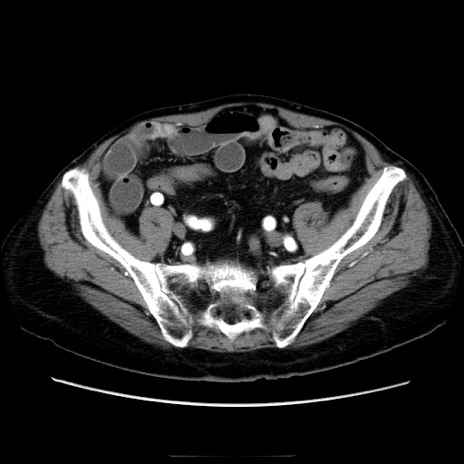

冠状断像

【症例】70歳代男性

【主訴】腹痛

【現病歴】肝硬変・肝細胞癌にてかかりつけの方。約9時間前に食後より腹痛出現。症状が徐々に増悪し、嘔吐出現したため来院。

【既往歴】肝硬変、肝細胞癌(RFA、TACE後)

【身体所見】意識清明、表情苦悶様、BT 36℃、BP 129/78mmHg、P 88bpm、SpO2 97%(RA)、右上腹部から心窩部にかけて圧痛あり、反跳痛なし、筋性防御あり。

【データ】WBC 5800、CRP 0.16